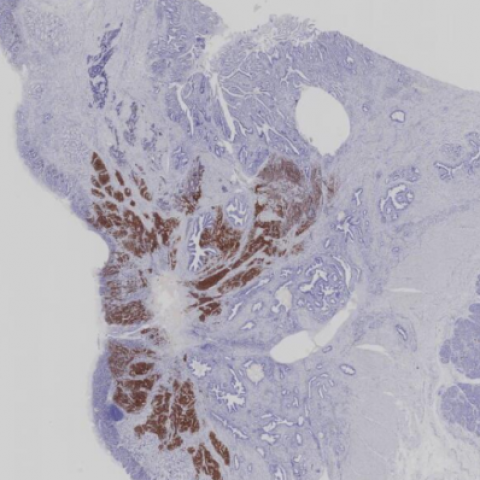

案例21 (7318)

性别:       年龄:72

临床资料: 患者2018年因非霍奇金淋巴瘤(右颈部淋巴结DLBCL, non- GCB)在 我院住院治疗,肠镜发现升结肠肿物,无腹痛腹胀,无粘液脓血便及排便不尽感, 未与处理。化疗四疗程后今复诊为进一步治疗入院。发病以来精神状态良好,体 重无明显变化,大小便正常。肠镜发现升结肠菜花状肿物,考虑结肠癌。

患者详情: 以“肠镜发现升结肠肿物”入院。

取材部位: 结肠

大体所见: 肠管一段,其中结肠长17cm,周径4.5-6.5cm,回肠长3cm,周径2. 5cm, 系膜脂肪组织大小15x6x1cm,未触及明显质硬结节,阑尾长5cm,直径0.4- 0. 5cm, 距结肠切缘11cm,可见隆起型肿物,外观呈息肉样,大小4. 5x3. 5x2. 5cm,切面灰白质中,目测累及肌层。

影像学检查: MR拟 结肠癌伴肠系膜淋巴结转移,肝内多发转移。活检结果“绒毛状-管状腺瘤”。

医院: 佛山市第一人民医院